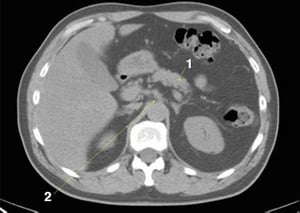

CT-Scan von Abdomen und Becken mit normaler Anatomie ohne Kontrastmittel (Folie 9)

1 = Pankreas; 2 = zöliakale Achse.

© Springer Science+Business Media